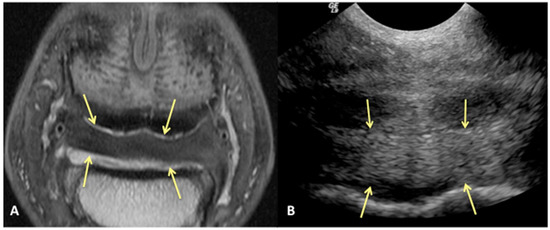

Results of sensitivity, specificity, and accuracy for comparisons of the findings of the DDFT, CSL, and navicular bursa are listed in Table 2. The low number of distal interphalangeal joint collateral ligament abnormalities resulted in low power for the statistic calculation, but prevalent findings are reported below. Ultrasound had the highest sensitivity for detecting enlargement and fiber damage of the dorsal aspect of the DDFT compared to identification of dorsal tearing of the DDFT on MRI, with a sensitivity of 85%, but it was less specific (60%) (Figure 1). Ultrasound was the least sensitive versus MRI to detect displacement (sensitivity 35%) of the CSL but was most specific for this finding (81%). Ultrasound also had a low sensitivity for detecting enlargement of the CSL (42%) but a specificity of 78% (Figure 2). Similarly, ultrasound was also less sensitive to detecting navicular bursa proliferation with a sensitivity of 47% but had higher specificity (78%) (Figure 3).

Figure 2. Transverse proton dense MR image (A) and corresponding transverse ultrasound image (B) of the collateral sesamoidean ligament. Palmar is on the top of the image, dorsal is on the bottom of the image, lateral is on the left. There is diffuse (mild) enlargement of the ligament (yellow arrows), positively identified with MRI and ultrasound.